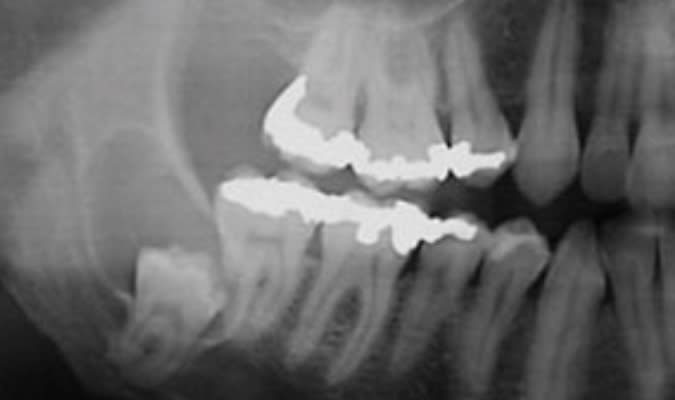

En même temps, avouez que très souvent quand les DDs sont sur l’arcade, elles ont une position improbable.

En attendant ,histoire qu’ils gardent un petit souvenir de moi , je leur laisse de temps en temps une crevasse quand j’y vais comme un bourrin . C’est pas mal, ça fait comme une réserve à nourriture :))

Fais moi vite un onlay ou une couronne sur la 7, elle va casser tôt ou tard... à moinsss que tu préfères implanter, attitude respectable :-))))

Tu penses bien que c’est prévu ^^ , d’autant plus que j’ ai zigouillé la partie D de l’amalgame en extrayant la 8 :)